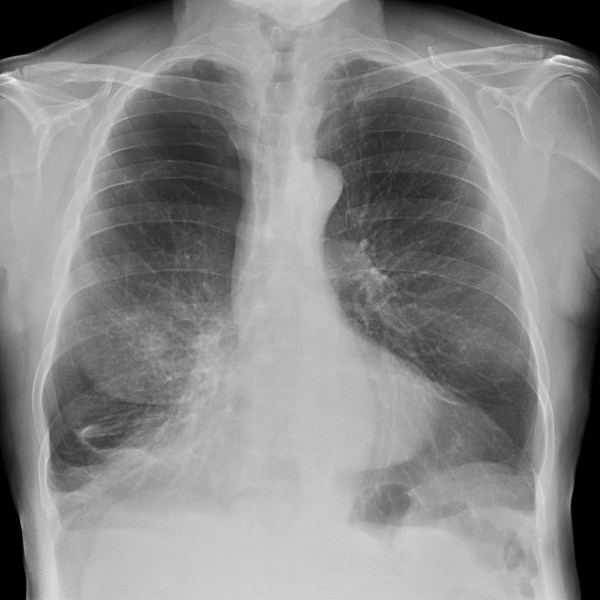

CASO: Operada de esofaguectomia y reconstrucción con coloplastia hace 3 meses. Sintomas de neumonía.

Hallazgos:

- De inicio llama la atención una densidad practicamente total del todo el hemitórax izquierdo, lo cual podría hacernos pensar que estamos ante una posible neumonía.

- Sin embargo el tórax está no está bien centrado, observar como la clavícula izquierda se encuentra casi en la mitad del pulmón, por tanto lo que vemos blanco es el mediastino ya que el tórax está rotado.

CENTRAJE:

El correcto centraje se determina comprobando que las extremidades internas de ambas clavículas equidistan de las apófisis espinosas vertebrales.

Mismo paciente, al cual esta vez se le ha tomado una radiografía en PA y en sedestación. Observar como las clavículas están equidistantes a las apófisis espinosas y como ha desaparecido el velamiento del pulmón izquierdo.

Por otra parte, paciente presenta una cardiomegalia y un discreto ensanchamiento del mediastino es probable relación con cambios postquirúrgicos.